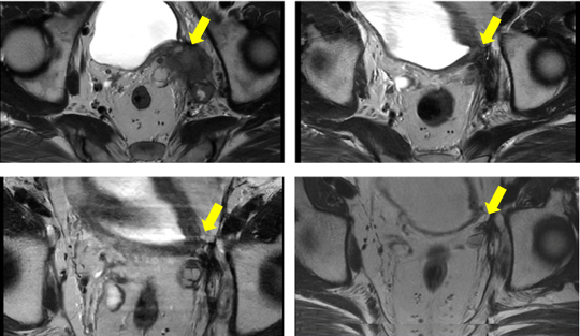

图4 连续随访图像

左上:治疗前 右上:治疗后1月

左下:治疗后1年 右下:治疗后3年